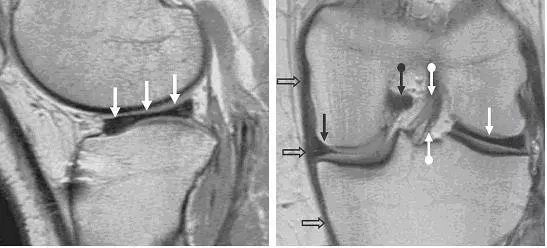

图 6 外侧盘状半月板

左图:矢状位片,可见外侧半月板(白色箭头)失去「领结样」形态,而呈现长条状,可与上图 2 左图对比。右图:冠状位片可更清楚对比,外侧半月板(白色直箭头)呈长条状而内侧半月板(黑色直箭头)呈正常的楔形。图中同时可看到其他软组织的相对关系,如前交叉韧带,可看到前交叉韧带前后束的明显分层(上下白色圆箭头),后交叉韧带(黑色圆箭头),内侧副韧带(空心箭头)。